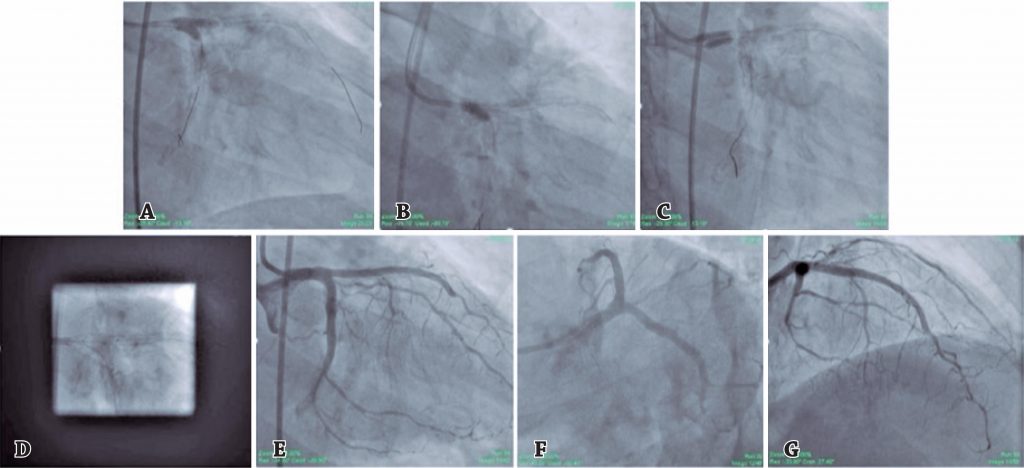

A bifurcação do tronco da coronária esquerda representa um dos locais mais desafiadores para os cardiologistas intervencionistas. Os stents são projetados e modelados para restaurar a geometria tubular, ao passo que a bifurcação do tronco da coronária esquerda é bem mais complexa, com diâmetros diferentes e secções transversais não tubulares. Em pacientes complexos, a estratégia de implante de dois stents é preferida à estratégia de stent provisional. O double-kissing crush é a técnica de duplo stent preferida. Apresentamos um caso em que a abordagem double-kissing foi usada no implante de stent na bifurcação do tronco da coronária esquerda com a técnica culotte , que resultou em bom resultado angiográfico e sem malaposição. O paciente manteve-se estável mesmo com 4 meses de acompanhamento.